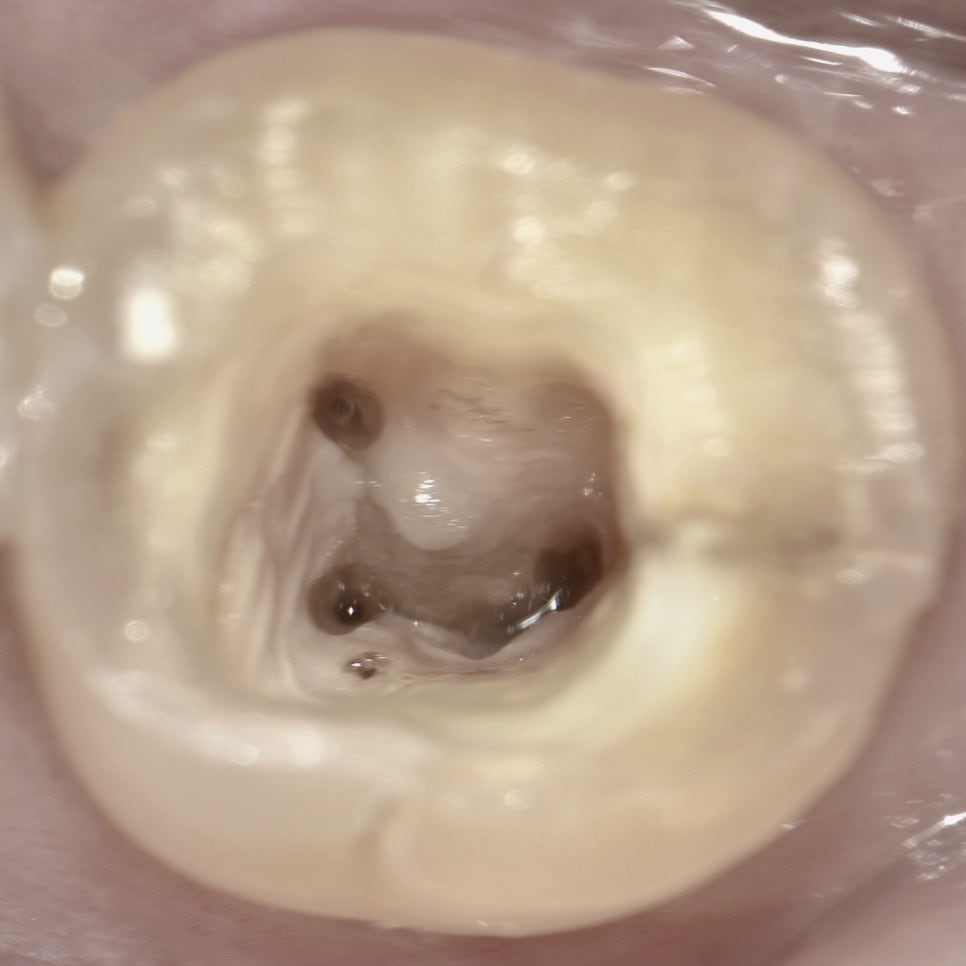

하악 7번 C형 캐널 빈도가 진짜 많아서 뜬금없이 찍어봤고요..

아 그리고 7번 엔도가 엄청 많은 게 왜 그런가 생각을 해봤는데, 다름 아닌 cracked tooth 때문이었다. 그동안 그냥 별생각 없이 "왜 이렇게 다 7번이지?"싶었는데 ㅋㅋ.. 위 사진에도 보면 디스탈에 아주 강한 크랙 라인이 있다. 그리고 근관 와동 안에서도 선명하게 관찰된다. 초진+A/O 날에 디스탈 월 쪽 크랙 라인 따로 포토 찍어서 환자분께 설명드렸던 기억이 난다. 하필 또 그게 DL canal로 이어지는 모양새라서 좀 더 예후가 안 좋을 것 같은 느낌도 드는데 어떨지 모르겠다. 더군다나 C-canal이라니. MB-DB 사이 isthmus 좀 더 긁어주고 NaOCl soaking도 더 해야겠다.